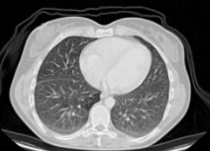

Table 3. Enhancement using dehazing and estimation of illumination for lung images of different datasets

Input Image

Output 1

Output 2

Final Enhanced Image

Lungs-1

Lungs-2

Lungs-3

Lungs-4

Note: This table is showing some lung images intermediate and final enhanced forms.

In Table 3, different dataset lung images' intermediate and final enhanced forms are showing. In the Table 4. we are showing the comparison between the calculated discrete entropy of enhanced images, PSNR, GMSD, and MCSD score for our proposed method as well as for Adaptive Gamma Correction with Weighting Distribution Method (AGCWD). In our proposed enhancement method, Entropy and GMSD score is always better than AGCWD method. High entropy is often desirable for images with complex textures and a lower value of GMSD indicates the improved quality of an image.